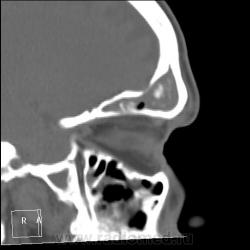

После пары менингитов на фоне синусита решили перебдеть. И вроде не зря... КТ: плотность содержимого в правой лобной пазухе 35-120 ед.Н. (мягкотканное с обызвествлением), в основной пазухе - 24 ед.Н (гнойной жидкости).

И пристеночный гайморит, и двусторонний этмоидит, и ринит, и односторонний сфеноидит, и фронтит, и очень тонкая костная пластинка между основанием передней черепной ямки и больной лобной пазухой - может быть реакция оболочек мозга...

По страшному снимку моему толком не видно, а вот на КТ множественные и разнообразные перегородки в пазухах видны хорошо. Я могу уверенно сказать только о следах жидкости в правой верхнечелюстной пазухе и субтотальном заполнении гомогенной жидкостью левой половины основной пазухи. Остальное, на мой взгляд, утолщение слизистой. Но на 100% утверждать не буду. В правой лобной я предполагаю (и только!) полипоз.

Вроде всё сказали…, но добавлю. Мне кажется, фронтит не односторонний. Эти плотные включения в правой, полипы и есть? Основных (клиновидных) пазух у каждого человека две, как и всех прочих. По обзорному снимку вижу левосторонний этмоидит. А по КТ не вижу. на каких кадрах он есть?

На 6 и 7 снимках... Справа затемнены передние ячейки решетчатых костей, слева - задние, слева процесс конечно интенсивнее.

Думаю, что полипы, "сидящие" на перегородке пазухи, сужу только по плотности - мягкотканные. А по поводу двух клиновидных пазух или разделения одной на перегородки - тут не всегда так: иногда бывает, что одна, а очень редко бывает, что и ни одной. Дайте неделю, сделаю подборку по основным пазухам на КТ.

хр.фронтит: справа с образованием обызвествленных полипообразных образований,слева- в виде утолщения слизистой оболочки. Решетчатый лабиринт клиновидной кости занят патологическим содержимым жидкостной плотности(?) с обеих сторон. Основная пазуха: справа - пристеночное утолщение слизистой, слева - тотальное заполнение. Определяется утолщение слизистой верхнечелюстных пазух, видимо воспалительного характера.